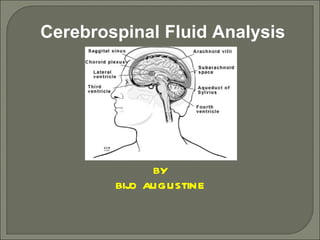

Ceribrospinal Fluid Analysis is a very important investigations in all laboratories. You can asses this ppt for your routine laboratory work.

- 1. Cerebrospinal Fluid Analysis BY BIJO AUGUSTINE